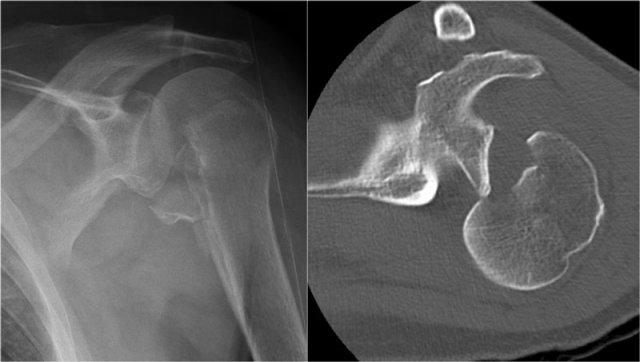

Gãy xương Bankart

Đây là hình ảnh sau nắn chỉnh.

Lưu ý đường gãy rất lớn của bờ ổ chảo kèm di lệch mảnh gãy.

Cuộn qua các hình ảnh.

Trên tái tạo mặt phẳng chếch vành tai và mặt phẳng đứng dọc, mảnh gãy di lệch của bờ ổ chảo được thấy ở vị trí 3-6 giờ.

Trên hình ảnh mặt phẳng vành tai, quan sát thấy một khuyết xương Hill-Sachs lớn.

Đây là khuyết xương do hậu quả của sự va đập bờ ổ chảo vào chỏm xương cánh tay.

Tái tạo 3D của tổn thương Bankart xương lớn tại vị trí 2 – 6 giờ.